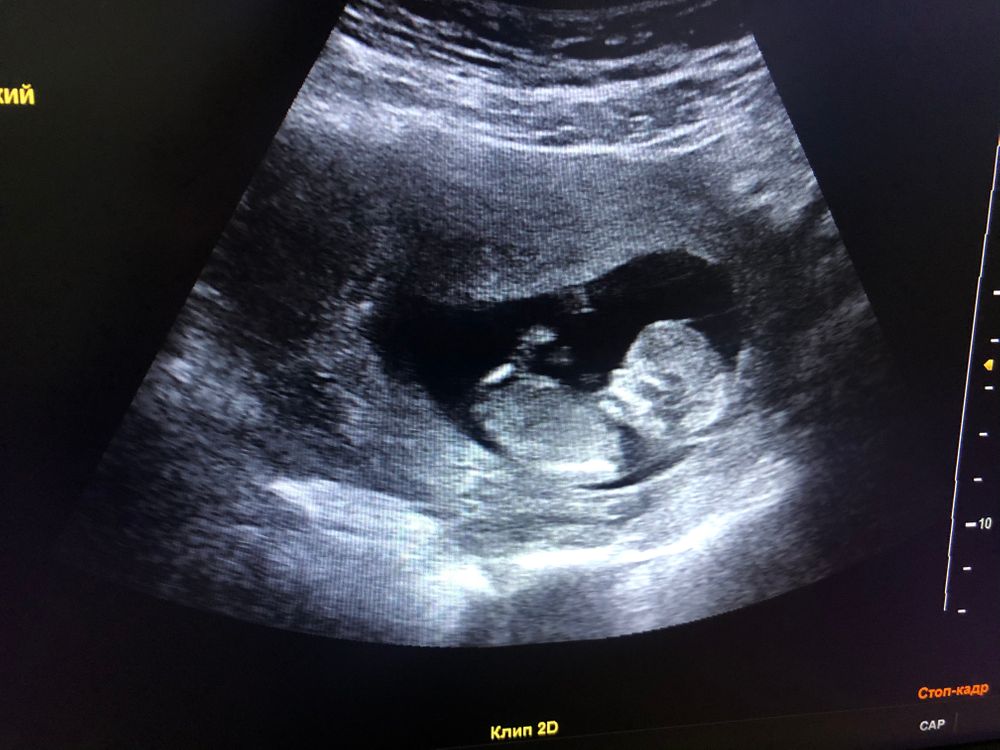

1 Скрининг

Насчёт пола не скажу, не разбираюсь вообще, но узи отличное и анализ крови тоже отличный! Все риски низкие и видите чёрный столбик полностью на зелёном фоне, это значит все супер! Когда он вылезает на желтый или красный, это значит могут к генетику отправить, вам это не грозит )))

Карина, УЗИ отличное. Насчёт крови - откройте почту. Там должен прилагаться графический файл. Через смску он не открывается, только сами анализы. Предполагаю девочку:))